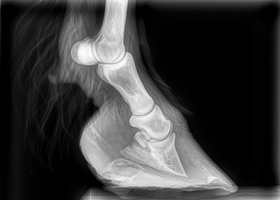

X-ray taken of a pony’s hoof suffering from Laminitis

Laminitis is a most common painful and debilitating condition affecting horses and ponies in the UK. Laminitis means inflammation of the laminae. The laminae are soft tissue structures found in the foot. They lie between the horn and the pedal bone and their purpose is to provide a secure attachment between these two vital structures. Inflammation of these laminae causes profound pain and greatly undermines their strength which means the pedal bone can rotate within the hoof capsule and even, in the worst cases, sink (or “founder”), a life-threatening situation.